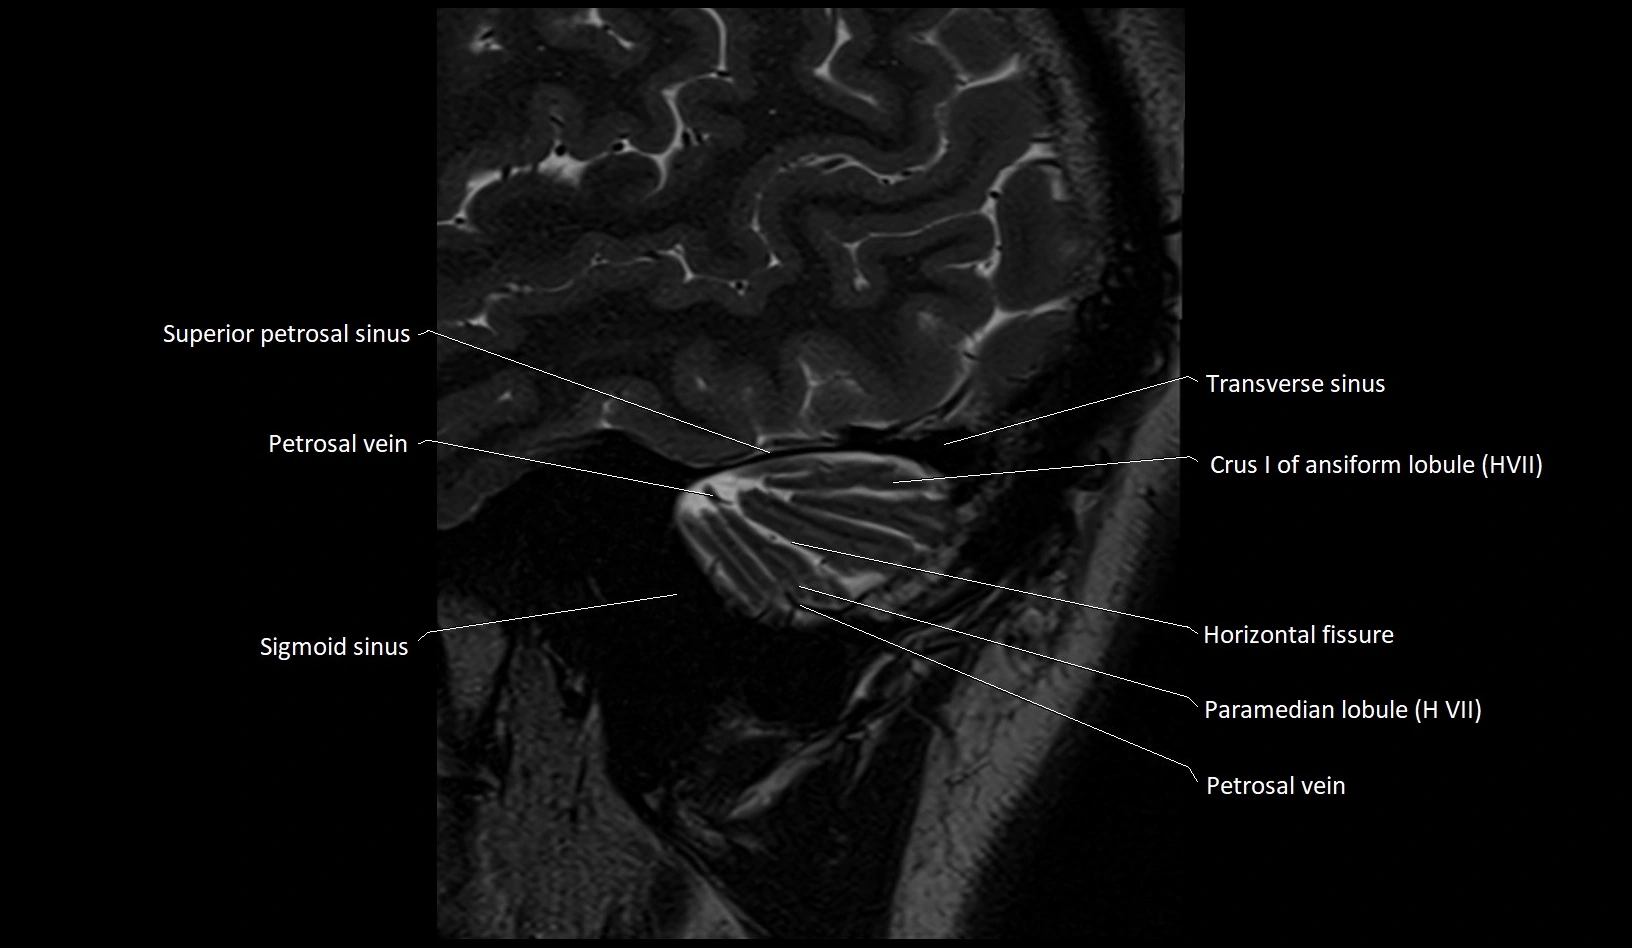

MRI images